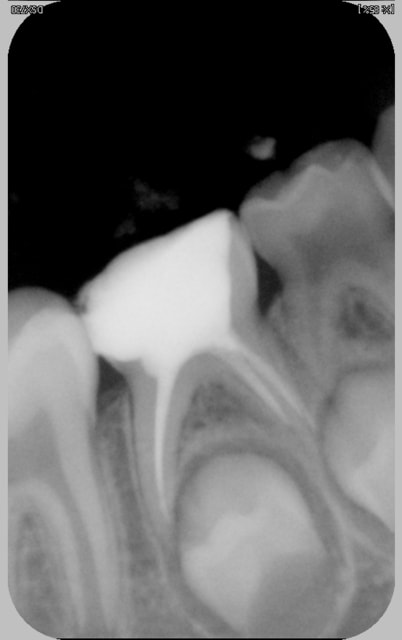

Quel stade et donc quel ttt pour cette lactéale plajmc - Eugenol

Aie pmqxbh - Eugenol

Eugenate gxljnp - Eugenol